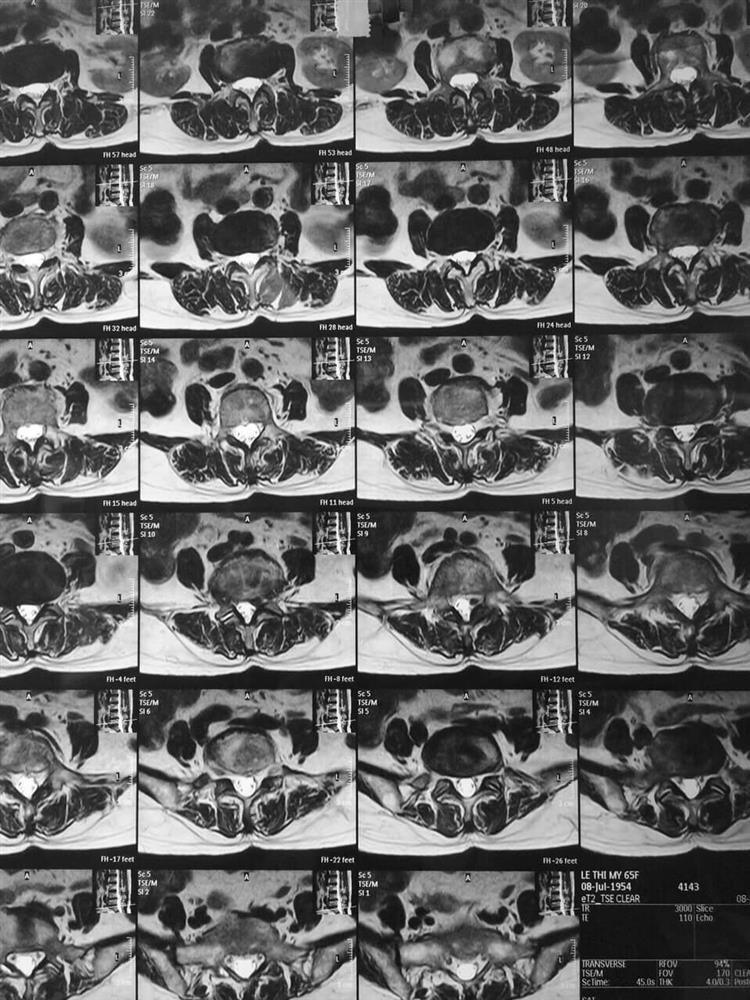

🎁Nhân một trường hợp bệnh nhân nữ 65 tuổi vào viện vì đau nhiều vùng cột sống thắt lưng, đau lan xuống đùi và cẳng chân bên trái, đi lại khó khăn và chỉ đi được vài mét bệnh nhân đã thấy đau tăng lên phải ngồi nghỉ.

Bệnh nhân đã được mở mảnh bên lấy khối thoát đĩa đệm làm vững cột sống bằng nẹp vis L4L5, sau khi mổ xong bệnh nhân hết đau lan xuống mông và chân chỉ còn đau tại vết mổ. Sau mổ 3 ngày bệnh nhân ngồi dậy tập đi lại sau 10 ngày bệnh nhân được cắt chỉ và ra viện!